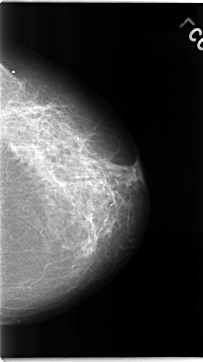

C_0072_1.RIGHT_CC

RIGHT_CC LINES 4656 PIXELS_PER_LINE 2704 BITS_PER_PIXEL 12 RESOLUTION 50 NON_OVERLAY